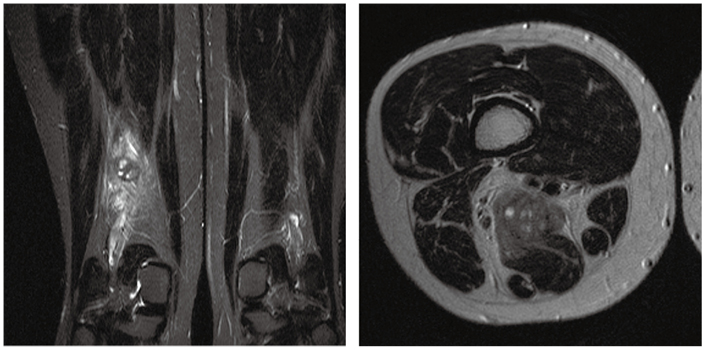

症例1

症例1の患者情報

70歳代,男性。

約1カ月前に階段をふみ外して右肩を受傷。以降,右肩痛で外来通院中に右大腿部痛が出現したため,MRI検査を施行した。現在,成人T細胞白血病リンパ腫治療中。